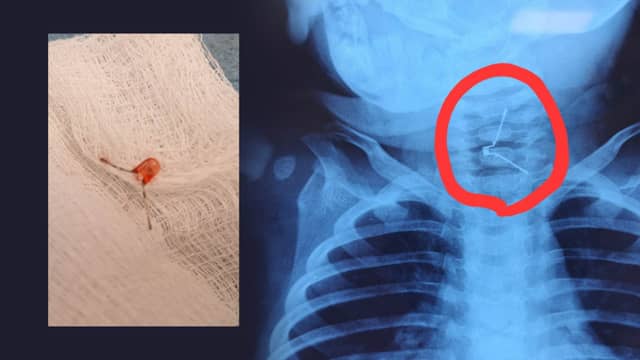

لە دهۆک منداڵێکی یەک ساڵ گڵۆپێک قووت دەدات و نەشتەرگەرییەکی دەگمەنی بۆ دەکرێت

منداڵێک لە ئاکرێ دوای ئەوەی گڵۆپێکی بچووک قووت دەدات...